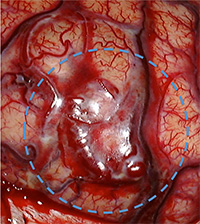

手術中の血管奇形部分の写真。青丸部分に拡張した血管網が見られます。(下図)

(画像は、日本赤十字社医療センター 脳神経外科 野村竜太郎先生のご好意による)